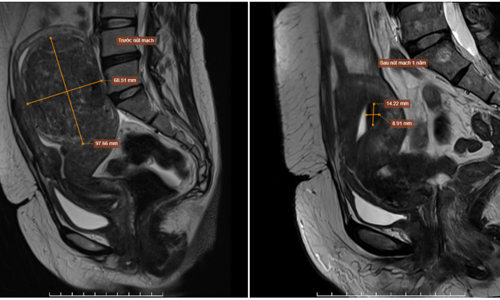

Uterine fibroids shrink after embolization VnExpress Ms. Lan, 48, had a uterine fibroid nearly 10 cm in size, which doctors successfully shrank using embolization, avoiding surgery.